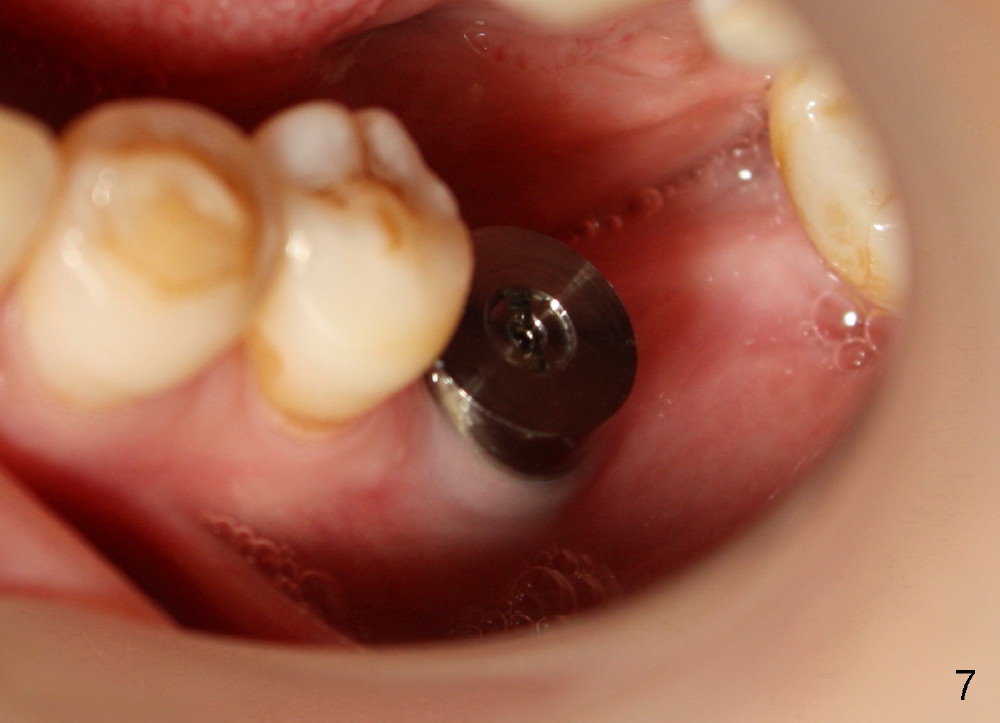

Seven days later, there is no sign of infection around the implant (Fig.6). Chronic infection prior to extraction may recruit our defense mechanism (such as white blood cells), which help prevent posteop infection. Two months postop, the gingiva is healthy around the implant (Fig.7,8).